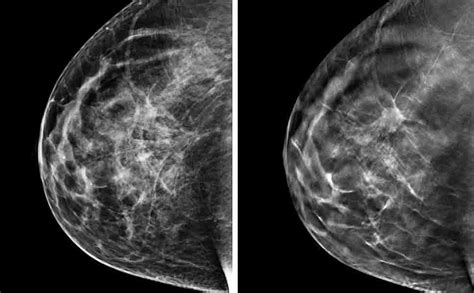

A differenza dei tumori invasivi che possono causare noduli o dolore, il carcinoma duttale in situ spesso non presenta sintomi evidenti. La maggior parte dei casi viene individuata tramite mammografie di routine o ecografie mammarie. La maggior parte dei pazienti con carcinoma mammario in stadio iniziale è asintomatica (priva di sintomi) e molti casi vengono scoperti durante lo screening mammografico. Con l’aumentare delle dimensioni la paziente potrebbe tuttavia avvertirne la presenza in modo accidentale, ad esempio durante la doccia: il carcinoma duttale infiltrante tende infatti a crescere come una massa coesa, tanto da essere spesso palpabile come un nodulo (ma è in genere più piccolo rispetto ad un tumore lobulare).

Se sospettato, il medico può ordinare:

- Mammografia diagnostica

- Ecografia